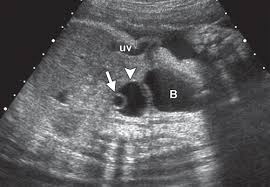

Transvaginal & pelvic ultrasound revealed bilateral ovarian cysts some of which are hemorrhagic and some are simple follicular.

The cancer was an estrogen secreting tumor. Many other symptoms can have similar symptoms such as endometriosis, fibroids uterine myomas, gastrointestinal conditions such as colitis, ibs, diverticulosis and benign ovarian cysts. what makes the situation more vexing is if the patient has only a few symptoms. A patient is pregnant 2. The cancer surgeon can remove the mass, and if it is determined to be cancer, can also remove lymph nodes to see if the cancer has spread. If a cyst grows or becomes complex (develops solid areas inside), it still may not be cancer but may need treatment. Pain is present on one side of the other 4. He doesn't think my reflux problem is related to my pelvic pain. If they are large, there may be some symptoms that affect the urinary tract and the reproductive system. This isn't the same as cause cancer; Meaning they are not cancerous. That extra estrogen caused the cyst to form on my other noncancerous ovary. Just because you've had an ovarian cyst or tumor doesn't mean you have, or will develop, ovarian cancer. Transvaginal & pelvic ultrasound revealed bilateral ovarian cysts some of which are hemorrhagic and some are simple follicular.

Simple Vs Complex Ovarian Cysts The Link To Ovarian Cancer Empowered Women S Health from images.takeshape.io While ovarian cancer has the lowest survival rate for all cancers, 92 per cent of patients will. It is impossible to tell the difference between ovarian cysts and ovarian cancer from the symptoms alone, but ovarian cysts are much more common. If a cyst grows or becomes complex (develops solid areas inside), it still may not be cancer but may need treatment. I was also diagnosed with diverticulosis following a ct a year before final diagnosis of stage 3 ovarian cancer. Transvaginal & pelvic ultrasound revealed bilateral ovarian cysts some of which are hemorrhagic and some are simple follicular. Most ovarian cysts are benign; Hcg levels are rising abnormally 3. I also had a vaginal ultrasound which supposedly showed nothing;

Conditions such as fibroids, endometriosis, infection, noncancerous ovarian cysts, and others can falsely elevate the value. Doctors at two hospitals thought christine coppa's terrible pain and leg tingling were caused by a small ovarian cyst. Many people refer to ovarian cancer as a silent killer, due to the fact that many of the symptoms can be mistaken for other issues by both doctors and women. Transvaginal & pelvic ultrasound revealed bilateral ovarian cysts some of which are hemorrhagic and some are simple follicular. Hcg levels are rising abnormally 3. Although the rate of ovarian cancer has been slowly falling over the past 20 years, the american cancer society's latest estimates are that about 21,290 women in the united states will receive a. I also had a vaginal ultrasound which supposedly showed nothing; To compound this difficulty, unlike breast cancer, where you may feel a lump, or cervical cancer, which can be picked up through a smear result, the key symptoms for ovarian cancer, particularly. Ovarian cancer is a scary disease—it affects about 20,000 women in the u.s. Also, endometriosis can cause cysts on the ovaries that may appear to be pelvic masses similar to ovarian cancer. If they are large, there may be some symptoms that affect the urinary tract and the reproductive system. Meaning they are not cancerous. They can be a part of the normal menstrual cycle, and can go away on their own.